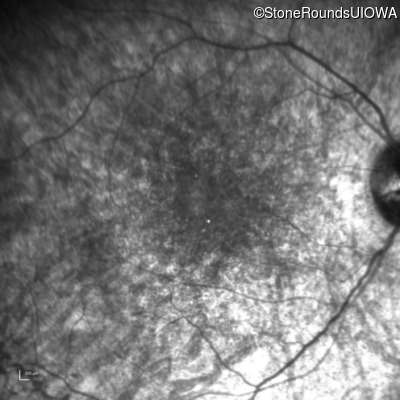

Infrared Fundus Photograph - Right - 10/140 sc

Exemplar